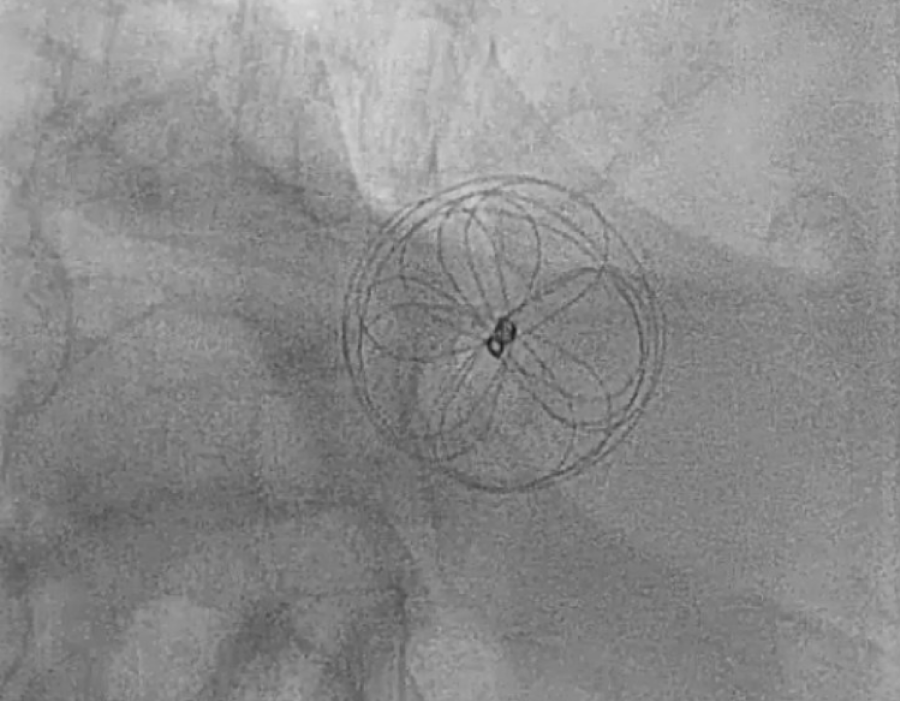

The patient’s clinical condition was consistent with Platypnea-Orthodeoxia syndrome based on the findings described above. A transthoracic echocardiogram indicated an ejection fraction (EF) of 51-55%, with mild left ventricular hypertrophy (LVH) and mild right ventricular dilatation. The bubble study was inconclusive. A transesophageal echocardiogram (TEE) revealed that the interatrial septum was aneurysmal, and a large PFO was visible on color Doppler imaging and following the injection of agitated saline contrast, as shown in figures 1 and 2. The patient underwent transcatheter closure of a patent foramen ovale using a 30 mm Gore Cardioform device, as depicted in figure 3 and 4. Immediately after the procedure, a repeat bubble study was conducted, which showed no bubbles crossing the patent foramen ovale (PFO). He was placed on dual antiplatelet therapy, with aspirin and clopidogrel for one month, followed by aspirin indefinitely. On the day of discharge, the patient was sitting upright in bed with oxygen saturation levels at 94% on room air and reported no shortness of breath. The patient was feeling much improved. The patient's care in the hospital involved a multidisciplinary approach that included teams from cardiology, pulmonology, and hospital medicine. Following hospital discharge, the patient had follow-up appointments in both the cardiology and pulmonary clinics and underwent a transthoracic echocardiogram (TTE) one month after the procedure. The left atrial cavity is moderately dilated. No patent foramen ovale was detected during the agitated saline injection. The patient did not report any breathing issues, and his oxygen saturation on the day of the follow-up was 94%.

Figure 4: Gore cardioform en-face view. View Figure 4